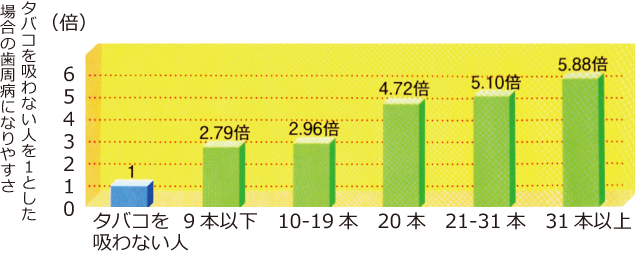

ヘビースモーカーだと歯周病に5倍なりやすい

1日あたりの喫煙本数と歯周病の関係

タバコを吸うとまず直撃されるのが口の中。

歯と歯ぐきにニコチンなどの有害物質が悪影響を与えます。体の抵抗力を弱めたり、末梢の血管を収縮させ、歯ぐきの血液循環を悪くしたりします。

また、タール(いわゆるヤニ)が歯にこびりつくと、歯磨きでは簡単に取れず、歯垢がつきやすい環境になってしまいます。

そのため、歯周病になやすく、治りにくくなります。

歯と歯ぐきのためにも全身のためにも、また、周囲の人のためにも、禁煙しましょう。